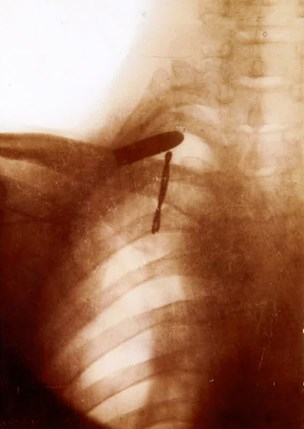

Memoir: ‘They soon had me up in the X-ray Room where they took my photograph, not [a] very good one of me but at least a very good one of the bullet, showing where it was and how close to the heart.’

‘I would maintain from the image available to me that the risk was to major vessels in the root of the neck rather than heart - bearing in mind that damage to these vessels is not to be recommended!! Subclavian artery (and vein would be very close by) with the Carotid Artery and Jugular vein to and from the head not at all far away!’

‘The other object on the X-ray is interesting, a wire-like thing. After magnifying the image there seems no evidence that his ribs were split and thus wired closed. Might it have been a marker taped onto the skin as a guide to positioning of the bullet tip to assist in the exploration? (It can be difficult to locate and any aid to localisation helpful. In my day used a sort of chicken wire grid sort of thing!) This one as the look of a ladies’ hair grip.’

Memoir: ‘[The morning after the operation Pilcher and the Ward Sister] removed my bandages in order to have a look and pull out the packing. I yelled, “For goodness sake leave my heart and guts inside and don’t pull them out as well” … Apparently, it had been a tricky job to remove the bullet. They had made an incision above my collarbone and had gone downwards under the ribs towards the heart and finally spooned out the bullet (which I still have) together with all the pus and other matter which had collected around it during the four months it had lain there.’

‘His notes indicate “incision above collar bone and gone down under my ribs towards my heart”. Not the type of incision to access heart space in my view, but ideal for the exploration of the collarbone area. The X-ray seems to show the bullet superficial to collar bone.

Dowding's X Ray Showing The Bullet

Dowding's x-ray showing the bullet

The amount of time the bullet had been there, there would be considerable reaction, indeed abscess cavity formation around the bullet which would be drained and cleaned out, carefully. It would then be packed with antiseptic soaked gauze (Bismuth Iodine Paraffin Paste often the antiseptic used). Since it was packed under the anaesthetic it would be packed firmly and the wound would not be completely closed to allow drainage. Removal of this packing would indeed be testing for him. Subsequent packing and dressing would be lighter and thus much more tolerable.

I remain perplexed by the angle and orientation of bullet in neck - bullet passing through jaw and lodging in neck /chest would be tip down not tip up as seen, unless transit through jaw had altered trajectory/orientation.’